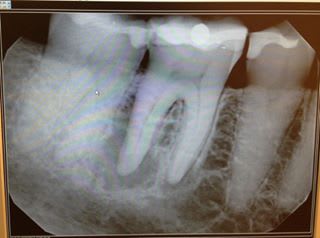

bonjour j ai recupéré un cas j ai posé deux implants 27,28et je doit me servir de ces deux la pour faire un bridge24,28

Problème: le patient m'a dit que c'était du branemark j ai commandé les pièces adéquates avec un conseiller nobel .

Patatras les pilers flottent j ai contacté un responsable NOBEL qui m a dit que c'était pas du Branemark.

j ai fait des recherches c est vrai qu 'il y a un branemark qui ressemble mais cela vouddrait dire que hexagone aurait été detruit ce que la responsable NOBEL m a dit etre impossible

il y aurait un Zimmer mais tout ne concorde pas avec un trou oval quant a celui qui a deux trous ovales il y aurait un IMZ mais celui ci a une surface lisse

Encore une fois, pour identifier un implant, il est nécessaire de connaître le type de connexion : pas le pilier, la connexion (hexagone ext, int, trilobe, créneaux... )

je sais bien mais avec les rx pouvez vous identifier le type de connexion

2/ à première vue comme çà, çà colle assez bien avec des zimmer...dont le col est pété...mais j'attends de voir des images plus nettes pour me prononcer...;-)

amha, c'est du tout bon à mettre à la benne...semblerait qu'il ne reste plus que le filetage interne...mais plutôt que les photos, déjà remet les radios comme il faut tel que je te l'ai dit...çà sera bien plus net et çà me permettra d'analyser ces implants dans le détail...